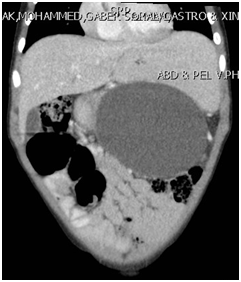

A 4-year-old boy weighing 14 kg, presented initially with abdominal pain, distension and vomiting of few days duration. Clinically, he looked sick, dehydrated, in respiratory distress, and his abdomen was markedly distended with severe tenderness all over the abdomen. The initial investigations in the local hospital showed WBC 4.6, Hb 12.5 g/dl, Amylase 2171, and lipase 1213. Abdominal ultrasound revealed pancreatic pseudocyst with moderate ascites. Abdominal CT-scan showed a large pancreatic pseudocyst (12X8X13cm) and massive ascites (Figure 1).

Figure 1A & 1B CT-scan showing a large pancreatic pseudocyst.

Note: The well formed wall and its adherence to the gastric wall.